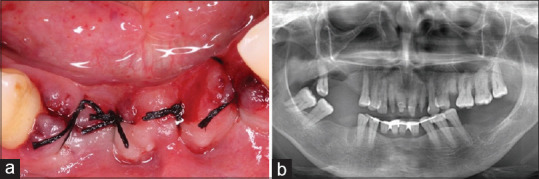

机会性感染在获得性免疫缺陷综合征中感染人类免疫缺陷病毒(HIV)的患者中很常见。本病例报告显示了一个患有牙周炎、艾滋病毒/丙型肝炎合并感染和念珠菌病的个体的临床病例,使用不同的药物并接受不规则的抗逆转录病毒治疗。几种局部和全身性疾病的结合突出了该病例的重要性以及卫生专业人员在艾滋病毒感染背景下了解这些综合病理管理的必要性。我们可以得出结论,由于与这些病理相关的致病机制,牙医了解艾滋病毒感染患者的牙周病是极其重要的。

Opportunistic infections are common in patients infected with human immunodeficiency virus (HIV) in acquired immunodeficiency syndrome. This case report demonstrates a clinical case of an individual with periodontitis, HIV/hepatitis C coinfection, and candidiasis, using different drugs and under irregular antiretroviral therapy. The combination of several local and systemic conditions highlights the importance of the case and the need for health professionals to know the management of these combined pathologies in the context of HIV infection. We can conclude that it is extremely important for dentists to be aware of periodontal diseases in HIV-infected patients, due to the pathogenic mechanisms associated with these pathologies.